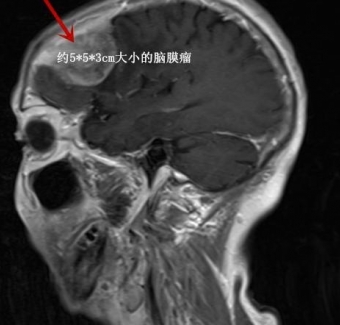

湖南八旬老人颅内巨大肿瘤,手术后医生用 3D 打印技术修补颅骨